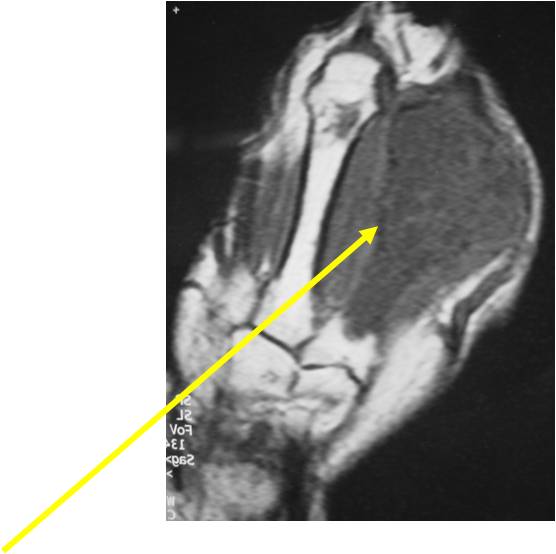

- MRI

- Lobulated margin

- Marked increased intensity long TR images

- Calcified chondroid – low intensity all sequences

MRI:

- Lobulated margin (Lobular Growth Pattern)

- T1 Weighted Images: Intermediate Signal Intensity

- Calcifications will be low signal

- T2 Weighted Images: High Signal Intensity

- High water content shows as high signal on T2 weighted images

- There should never be any cortical destruction nor a soft tissue component. If this exists then the tumor must be a chondrosarcoma.